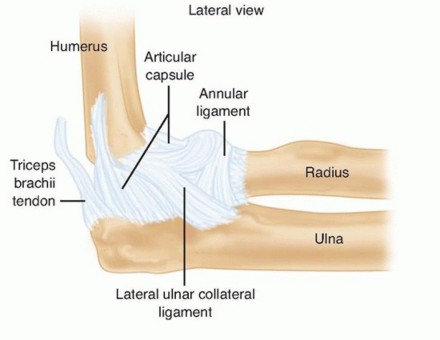

Open Reduction and Internal Fixation of Supracondylar and Intercondylar Fractures